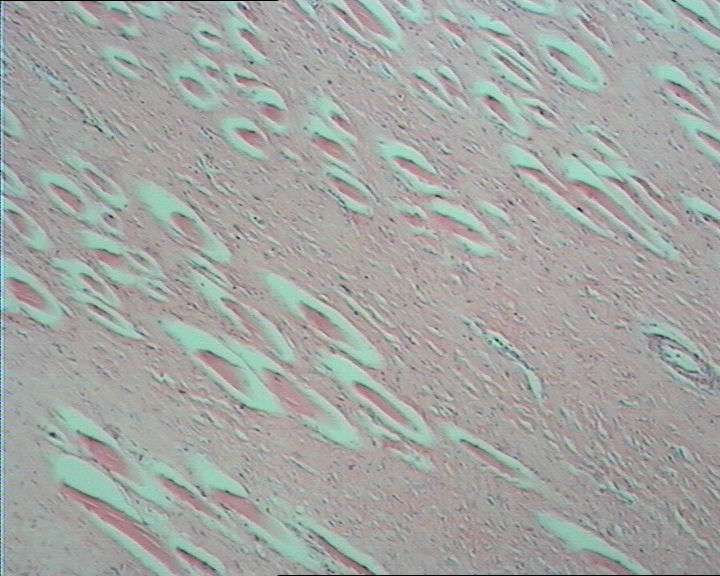

图2

无包膜 3.8cm*3.0cm*2cm 切面灰白淡黄相间

右肘部肿物,无包膜,3.8cm*3.0cm*2cm,切面灰白淡黄相间。